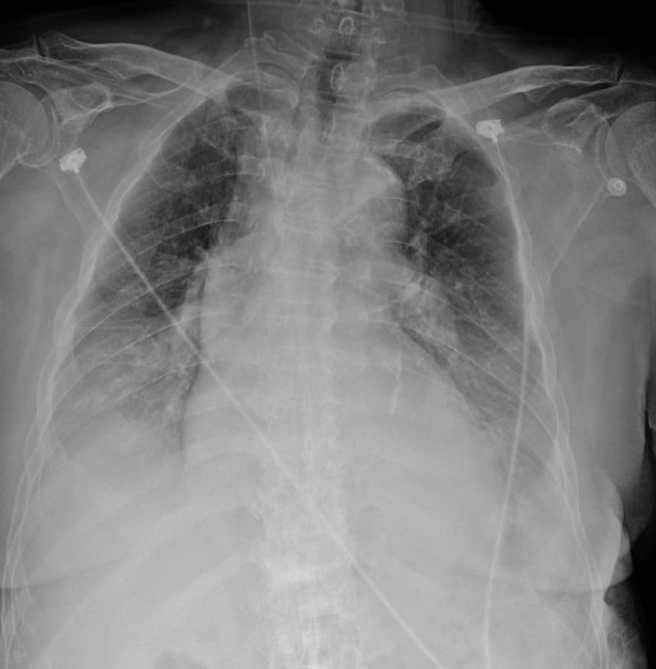

本土疫情遍地烽火,新光医院急诊科主任张志华表示,一名老太太未打过新冠疫苗,确诊后肺部呈现一片白,令他忍不住想起去年5月爆发的Alpha疫情时的情景,呼吁还没打疫苗或未打满3剂的长者,加速施打预防重症。

张志华上周六(21日)于个人脸书指出,一名PCR筛检为阳性确诊的老太太,没有打过任一剂新冠疫苗,院方安排照肺部X光,发现呈现一片白色,令他忍不住说,「挺吓人的,像极了去年5月爆发的Alpha疫情。」

张志华说,去年5月爆发的疫情,当时疫苗不足,许多人未打疫苗确诊后,X光检查肺部整片发白,有纤维化现象,张志华呼吁,没打疫苗或未打满3剂疫苗的长者,尽快打疫苗预防重症。

贴文曝光后,引发网友讨论,「想想还好去年五月有守下来」、「这肺部X光片感觉烟雾弥漫,好像谁在抽烟」;留言中也有人好奇老太太是否有慢性病史及实际年龄,不过张志华并没有进一步说明。